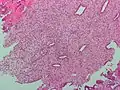

.jpg) Endometrioid adenocarcinoma from biopsy. H&E stain.

Endometrioid adenocarcinoma from biopsy. H&E stain. -